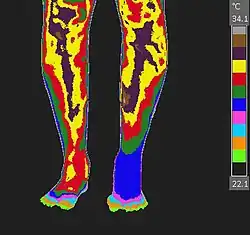

CRPS, RSD, Medical Thermology, Thermography

CRPS-RSD of the left foot imaged with medical thermology during a cold pressor test.

Examples of neuro-musculoskeletal indications for medical thermology include Reflex Sympathetic Dystrophy (RSD), Chronic Regional Pain Syndrome (CRPS), Dysautonomia, Migraine, Fibromyalgia (and other weather-sensitive pain syndromes), thoracic outlet syndrome, and vaso-motor migraine/headaches such as Barré-Liéou syndrome. This is especially true when used to monitor the results of a cold stress (cold presser) test.[3]